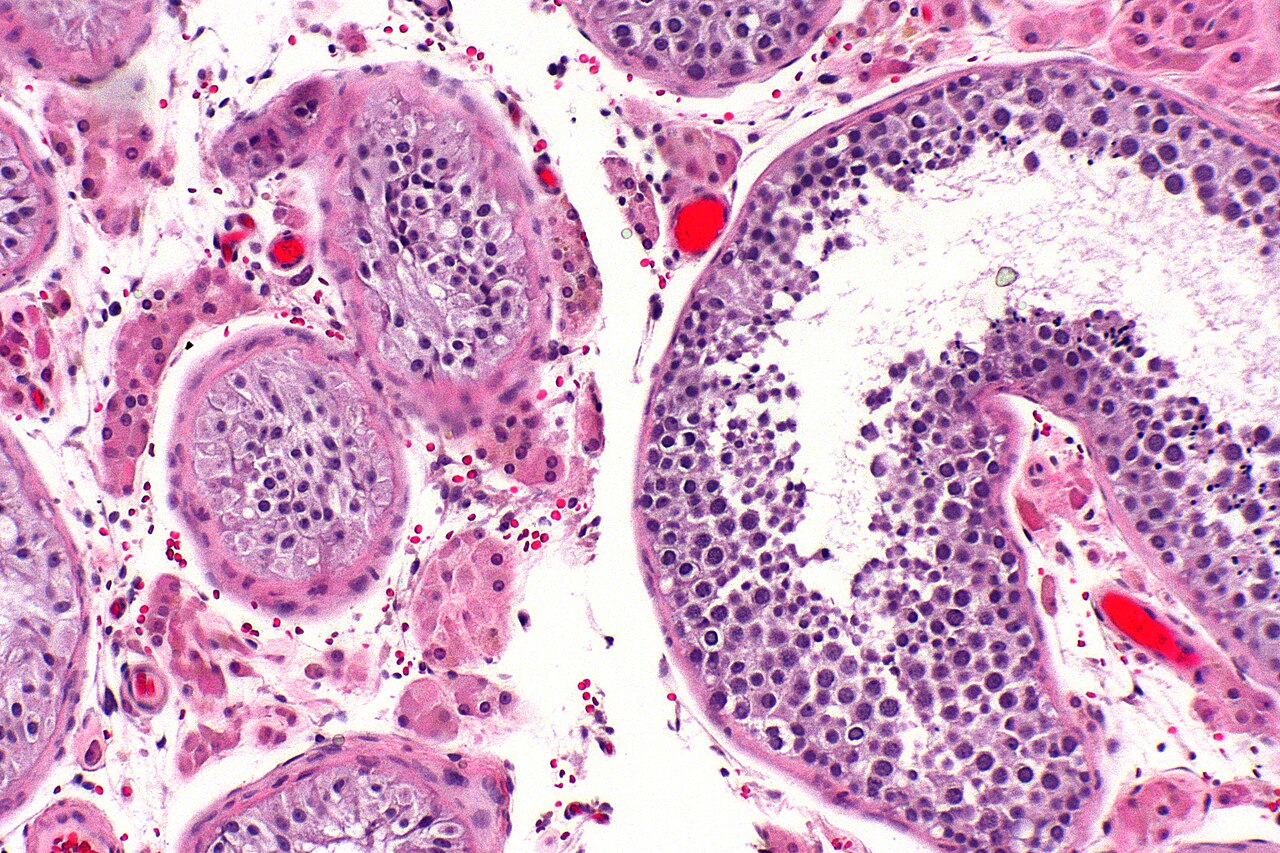

TRT Testicular Atrophy & Infertility: What Men Need to Know